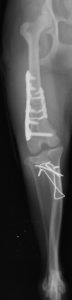

(左) 8ヶ月齢トイプードル 膝蓋骨内方脱臼グレード4 (右)一般的な膝蓋骨脱臼の治療手術に加え大腿骨の骨きりを実施した。(下動画) それぞれ術前の歩様と手術後4年の歩様